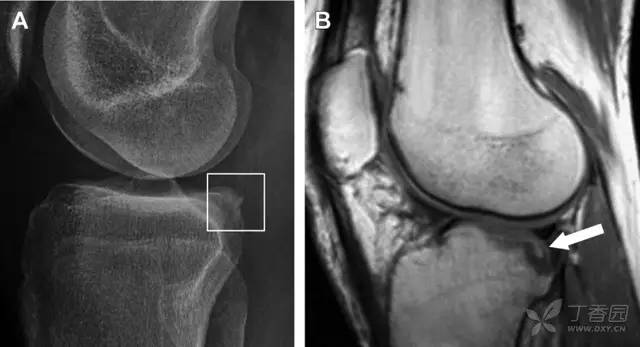

胫骨后外侧小片骨皮质的压缩性骨折,可能是旋转移位损伤的唯一证据(图 3)。这种骨折在常规膝关节平片很难发现,若怀疑存在骨折,行下肢内旋斜位片检查可诊断。

图 3 胫骨后外侧碎片骨折

A 正位片示胫骨后外侧处可见一压缩骨折的小碎片(方框)。这是胫骨撞击股骨外侧髁旋转移位时所致。B 另一位患者的 MRI 矢状位 T1 加权像示胫骨后外侧骨折碎片(箭头)。